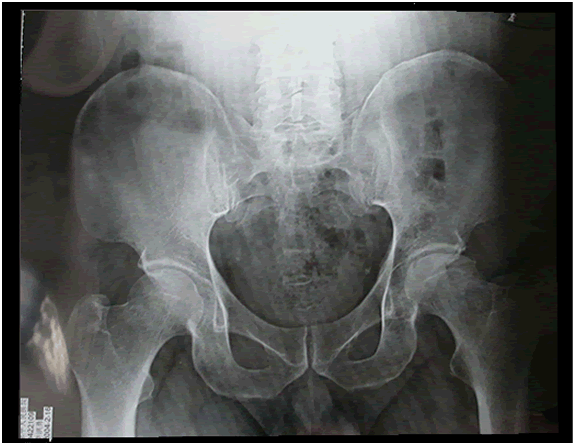

治愈后

卢某某:男,47岁,烟台市牟平区莒格庄崖子村人,患双侧骨股头坏死,于2004年2月

16日开始服用李氏活血补肾丹,8个疗程后,2004年10月12日复诊明

显好转,可不拄双拐走路,现仍继续服药。